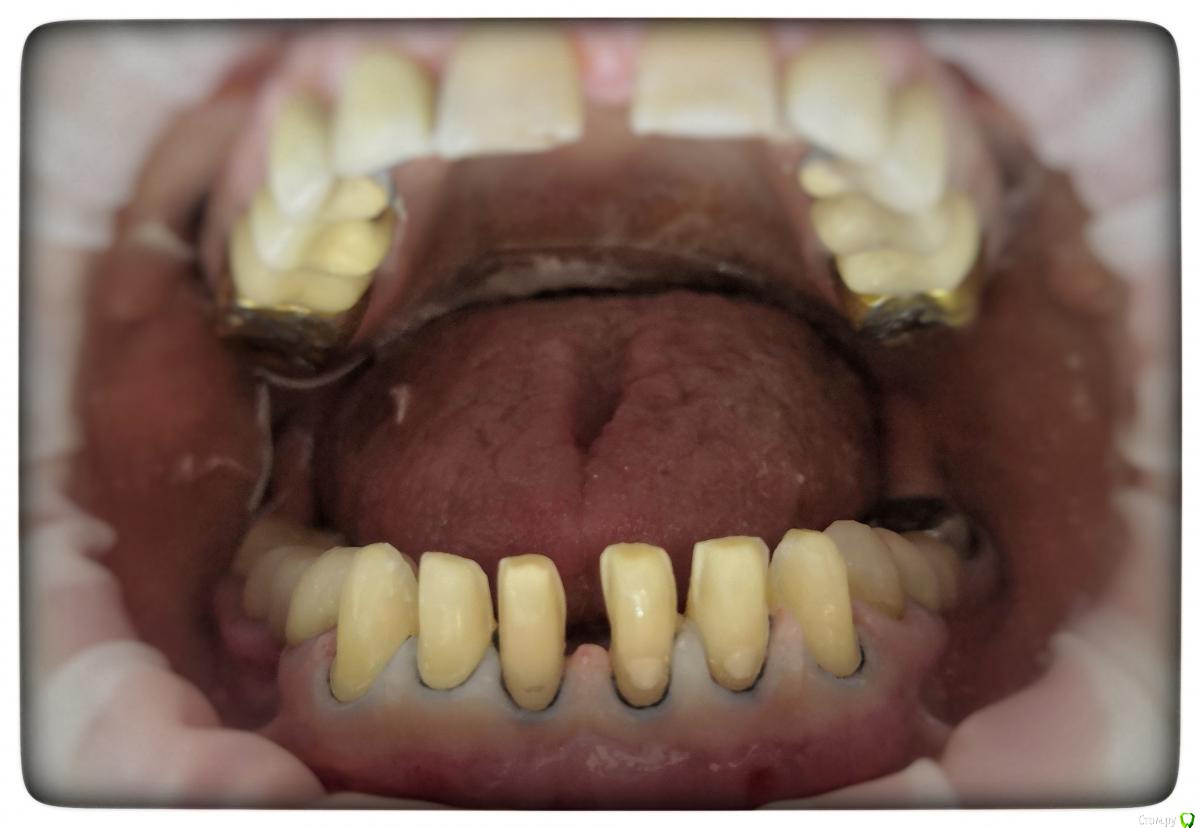

Sagaydak Aleksandr Опубликовано 27 марта, 2019 Автор Поделиться Опубликовано 27 марта, 2019 Фото Ссылка на комментарий

Sagaydak Aleksandr Опубликовано 27 марта, 2019 Автор Поделиться Опубликовано 27 марта, 2019 . Ссылка на комментарий

Sagaydak Aleksandr Опубликовано 27 марта, 2019 Автор Поделиться Опубликовано 27 марта, 2019 Препарировал через мокап. Ссылка на комментарий